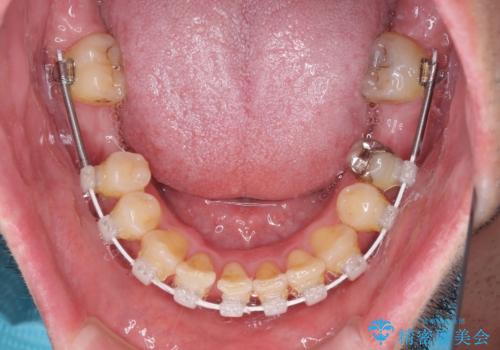

咬み合わせは受け口傾向であり、上顎前歯の叢生が顕著であったことから、第1小臼歯抜歯による矯正治療も検討しましたが、下顎大臼歯を左右ともに抜歯するため、非抜歯による矯正治療を行うこととしました。

矯正治療でインプラント埋入を行い、矯正治療後に気になる前歯と合わせてオールセラミッククラウンによる補綴治療を行うこととしました。